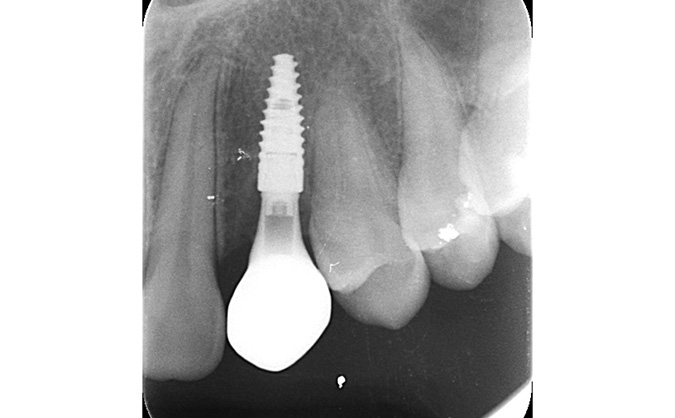

症例10

治療前

治療後

治療後のレントゲン写真

治療後の口腔内写真

主訴 噛むと痛い

治療期間 6ヶ月~8ヶ月

治療費 450,000円

治療内容 インプラント精密検査(口腔内写真/CT/模型)

抜歯 骨補填材(足りない骨を人工骨として補填)

インプラント治療

治療のリスク 骨の状況次第で抜歯と同時に人工骨填入が必要となる場合があります。

主訴

噛むと痛い

治療期間

6ヶ月~8ヶ月

治療費

450,000円

治療内容

インプラント精密検査

(口腔内写真/CT/模型)

抜歯 骨補填材

(足りない骨を人工骨として補填)

治療のリスク

骨の状況次第で抜歯と同時に人工骨填入が必要となる場合があります。

インプラント精密検査(CT撮影)

治療内容 当院ではCT撮影を行いシュミレーションを行い正確なインプラントの埋入位置の決定し手術を行っております。

当院ではCT撮影を行いシュミレーションを行い正確なインプラントの埋入位置の決定し手術を行っております。